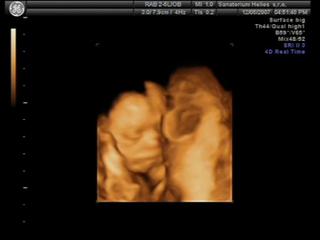

@valmark Já na 3D byla s klukem a to byla paráda, jak tam byl samotnej. Teď s klukama jsem šla taky, ale spíš jen proto, abych měla pro ně stejný fotečky jako pro Karímka.. kluci byli příčně, každej s hlavou na opačný straně, tak mám fotku jednoho s nohou toho druhýho v obličeji..asi prvních 5minut bylo něco poznat, ale pak se tam šmrdolilo pořád nějak moc rukou a nohou najednou, byla to taková změť , že se nic moc nedalo poznat. Ne že bych byla tak moc zklamaná, ale asi bych do toho s dvojčatama znova nešla..Zkusím tu pěknou fotku někde vyhrabat a poslat na ukázku..

Jinak my na tom 3D utz byli a taky bych ho ozelela. U tech dvojcatek nic moc,vsechno se tam mele pres sebe,ze tam neni nic moc poznat. Takze z tech fotek jsme rozeznali maximalne oblicej a zbytek byl takovej maglajs zlute hmoty🙂

@atreides Byla jsem přesně ve 24+0tt. Každýho chlapečka mám jednou vyfocenýho a ani jsme si nemohli z fotek vybírat, prvních 5minut sestřička chytla každýho kluka jednou a pak už nic..jen chumel rukou a nohou ☹

Tak tohle jsou moji chlapečci..na tý druhý fotce je vidět nožička prvního chlapečka, kopal bráchu do obličeje 😀